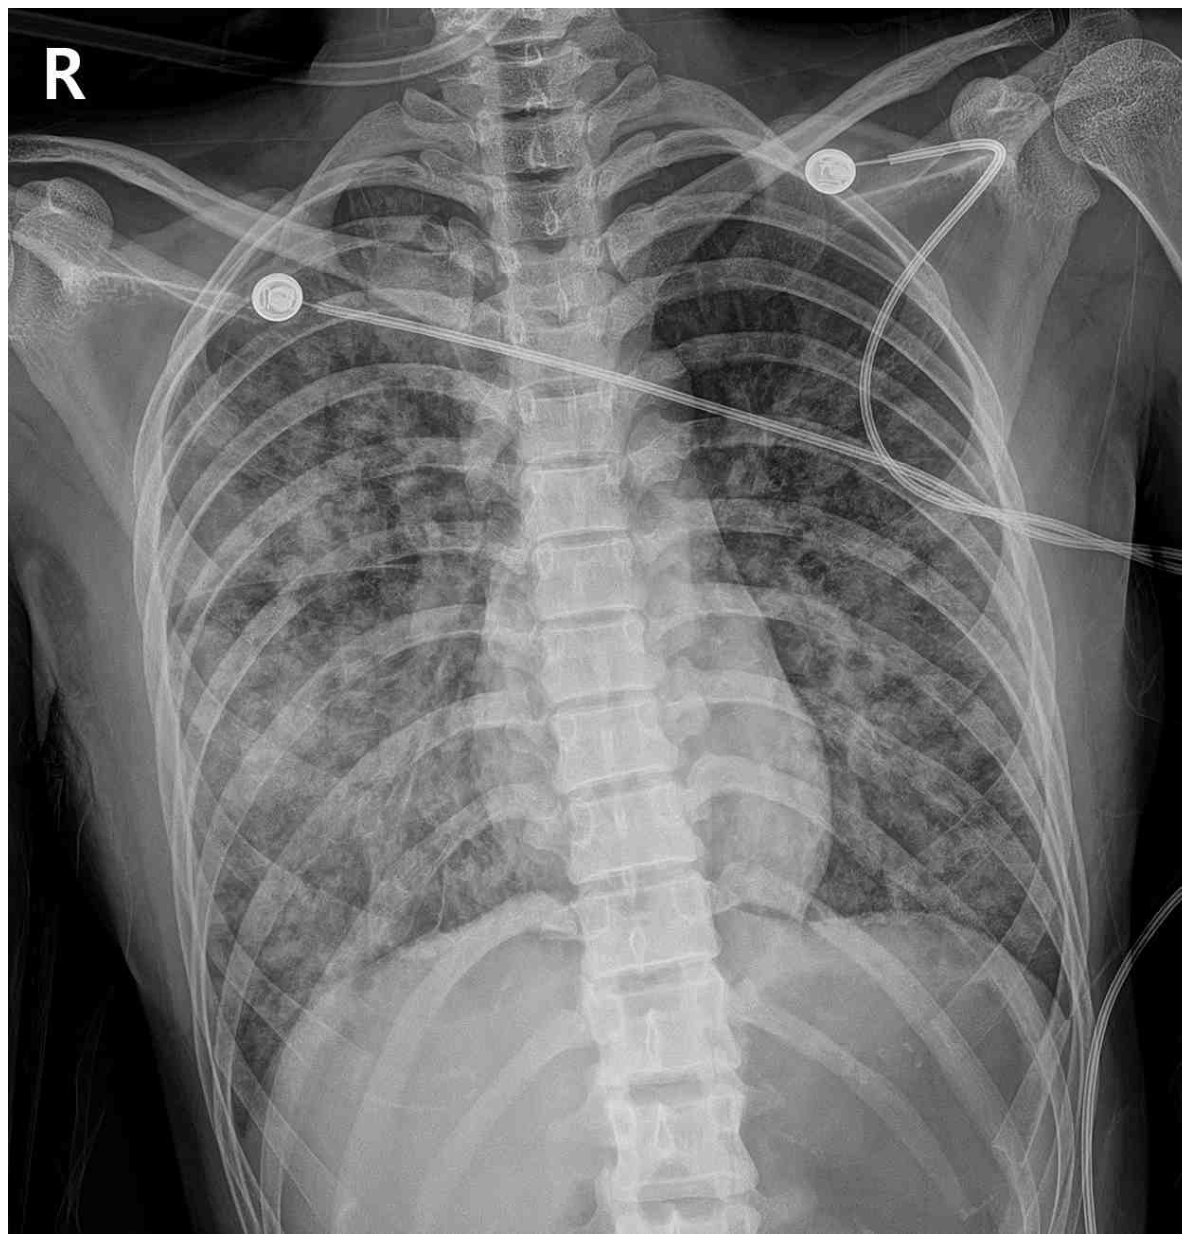

46세 여자가 2일 전부터 숨이 찬다며 병원에 왔다. 5일 전 콧물이 나고 근육통과 열감이 있었다. 3일 전부터 가래 섞인 기침을 하고 점점 심해졌다고 한다. 비흡연자이다. 혈압 80/50 mmHg, 맥박 116회/분, 호흡 36회/분, 체온 38.2°C 이다. 진찰 중에 자꾸 자려고 한다. 양쪽 가슴에서 거품소리가 들린다. 가슴 X선사진과 가슴 컴퓨터단층촬영 사진이다. 검사 결과는 다음과 같다. 처치는?

CXR: Bilateral diffuse opacity

• 더불어 1주일 이내 호흡증상이 시작되었고, CXR 및 chest CT 등 영상 소견에서 bilateral diffuse opacity를 관찰할 수 있으며, BNP가 참고치 이내로 심부전 및 체액 과부하의 증거가 없고 PaO2/FiO2 = 52/0.5~0.6 ≤ 300mmHg으로 hypoxemia가 확인된다. 따라서 해당 증례는 Berlin definition의 네 가지 기준을 모두 만족하므로 급성호흡곤란증후군으로 진단할 수 있다.